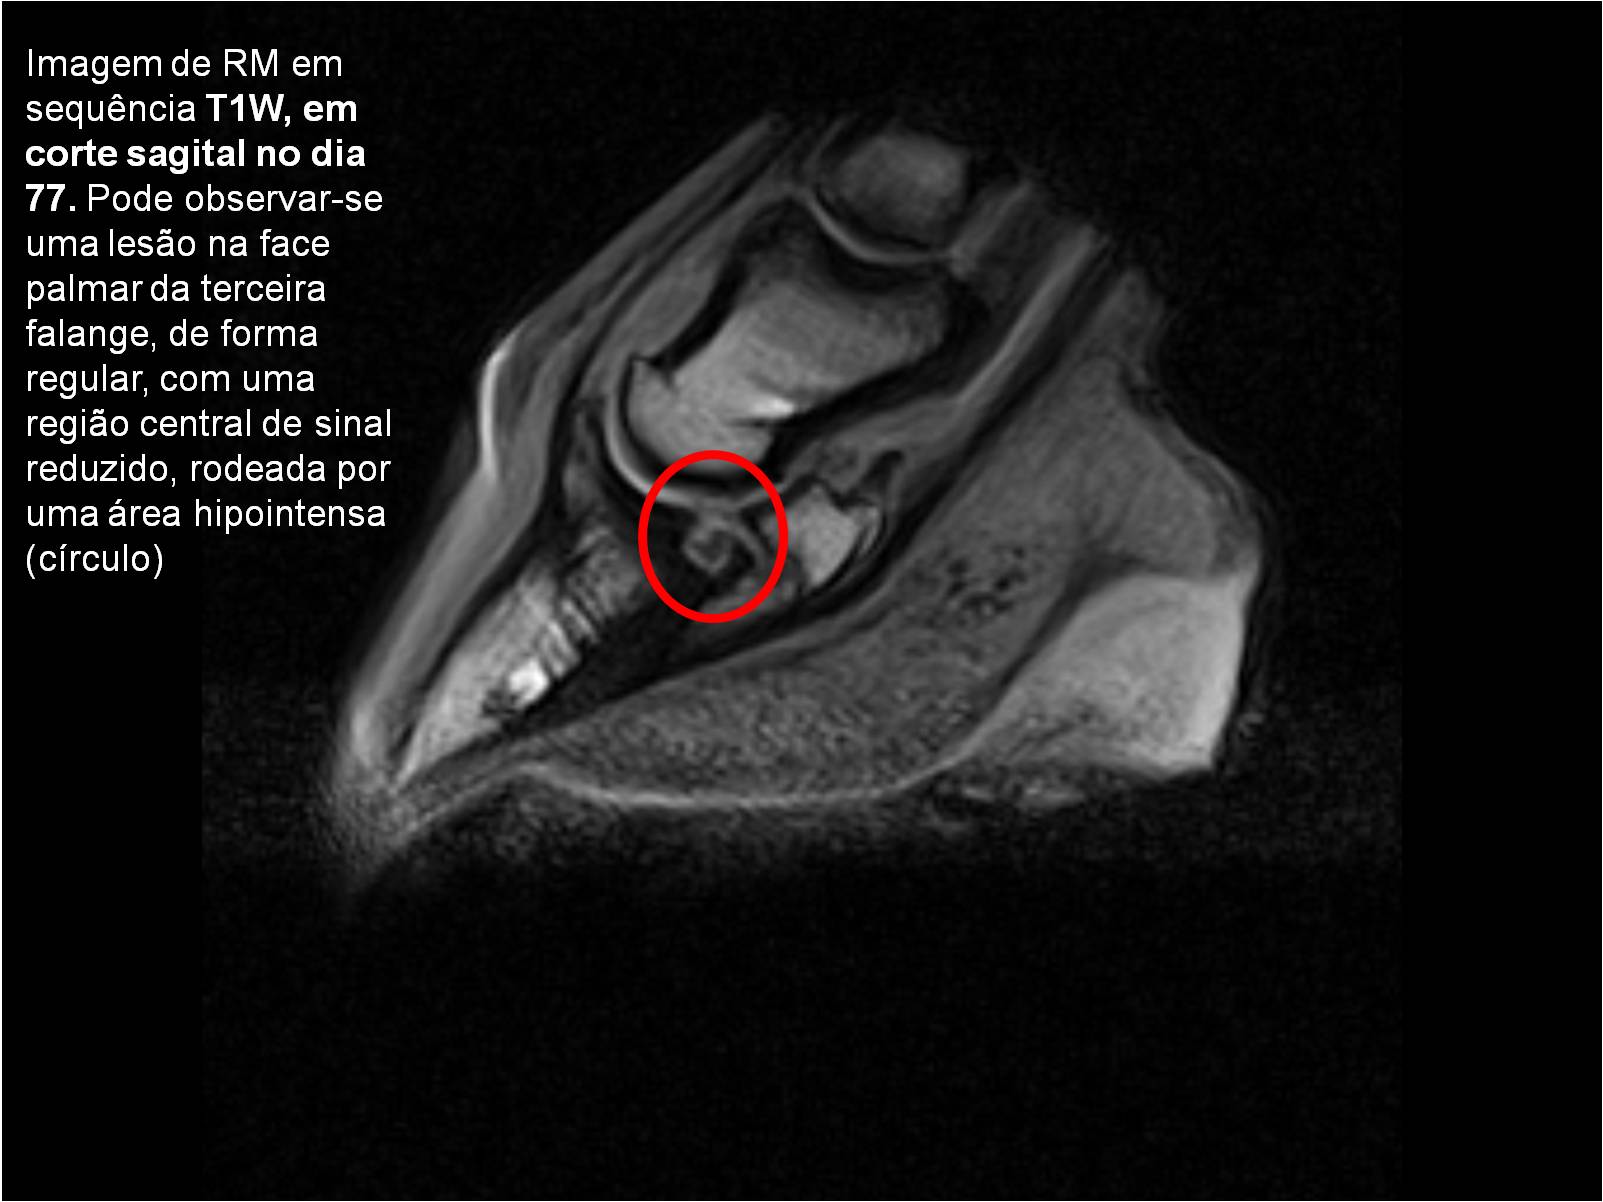

Publisher: Universidade de Évora

Abstract: O relatório de estágio encontra-se estruturado em três partes distintas. A primeira parte faz a caracterização das infraestruturas e funcionamento do Hospital Veterinário de Equinos de Lüsche, Oldenburg, Alemanha, assim como a análise casuística dos casos clínicos acompanhados durante os 6 meses de estágio. A segunda parte consiste de uma revisão bibliográfica sobre quistos do osso subcondral em equinos. Por fim, a terceira parte consta da apresentação e discussão de um caso clínico, nomeadamente o diagnóstico e acompanhamento imagiológico, por ressonância magnética, de um quisto subcondral na terceira falange num cavalo adulto; ### Abstract Equine Practice- Subcondral bone cyst of the third phalanx This internship report is divided in three parts. The first part characterizes the infrastructure and function of the Equine Hospital Lüsche, Oldenburg, Germany, as well as the casuistic of the clinical cases accompanied during the 6 month internship. The second part consists in a bibliographic review of cystic lesions of the subchondral bone in equines. The third part consists in a case report, the diagnostic and imagiological accompaniment, by use of magnetic resonance imaging, of a subchondral bone cyst in the distal phalanx of an adult equine.